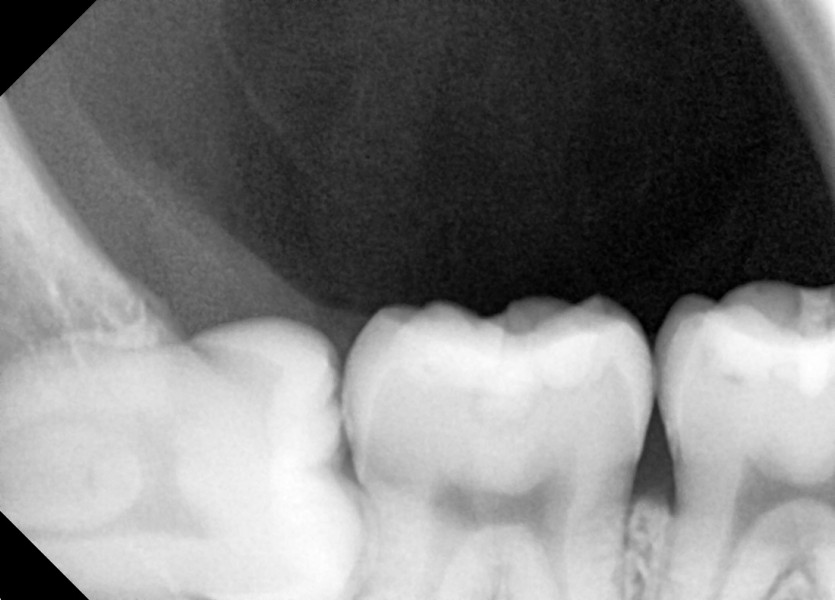

#18,48 사랑니 발치

구강 외과 전문의가 당일 발치했습니다.